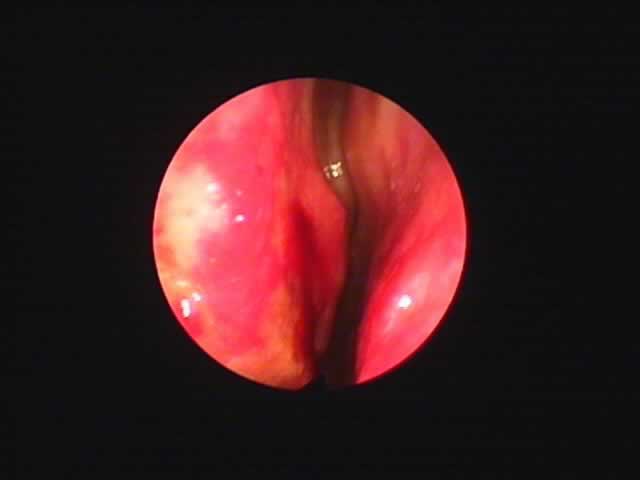

![]() |

| 7月16日 かなり縮小 | 両手術直後(縮小不十分なため追加焼灼、8月9日) | 9月8日 著明に縮小しいびき消失しているとのことです |